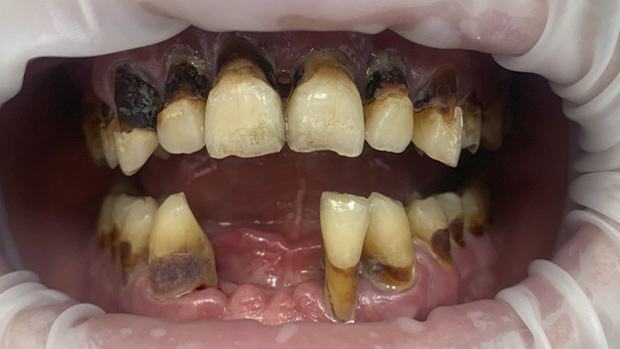

Причина обращения пациента: эстетические дефекты, неприятный запах изо рта, затруднения при пережевывании пищи, оголение корней зубов.

Особенность: 3 нижних передних резца отсутствовали, стоматофобия – боязнь стоматологического лечения.

2 года назад ко мне обратился пациент К. с жалобами на эстетические дефекты, неприятный запах изо рта, затруднения при пережевывании пищи, оголение корней зубов. Три нижних передних резца отсутствовали. При осмотре и после проведения КТ было установлено, что все зубы разрушены настолько сильно, что уже не подлежат терапевтическому лечению. Соответственно, проведение протезирования с опорой на собственные зубы было невозможно.